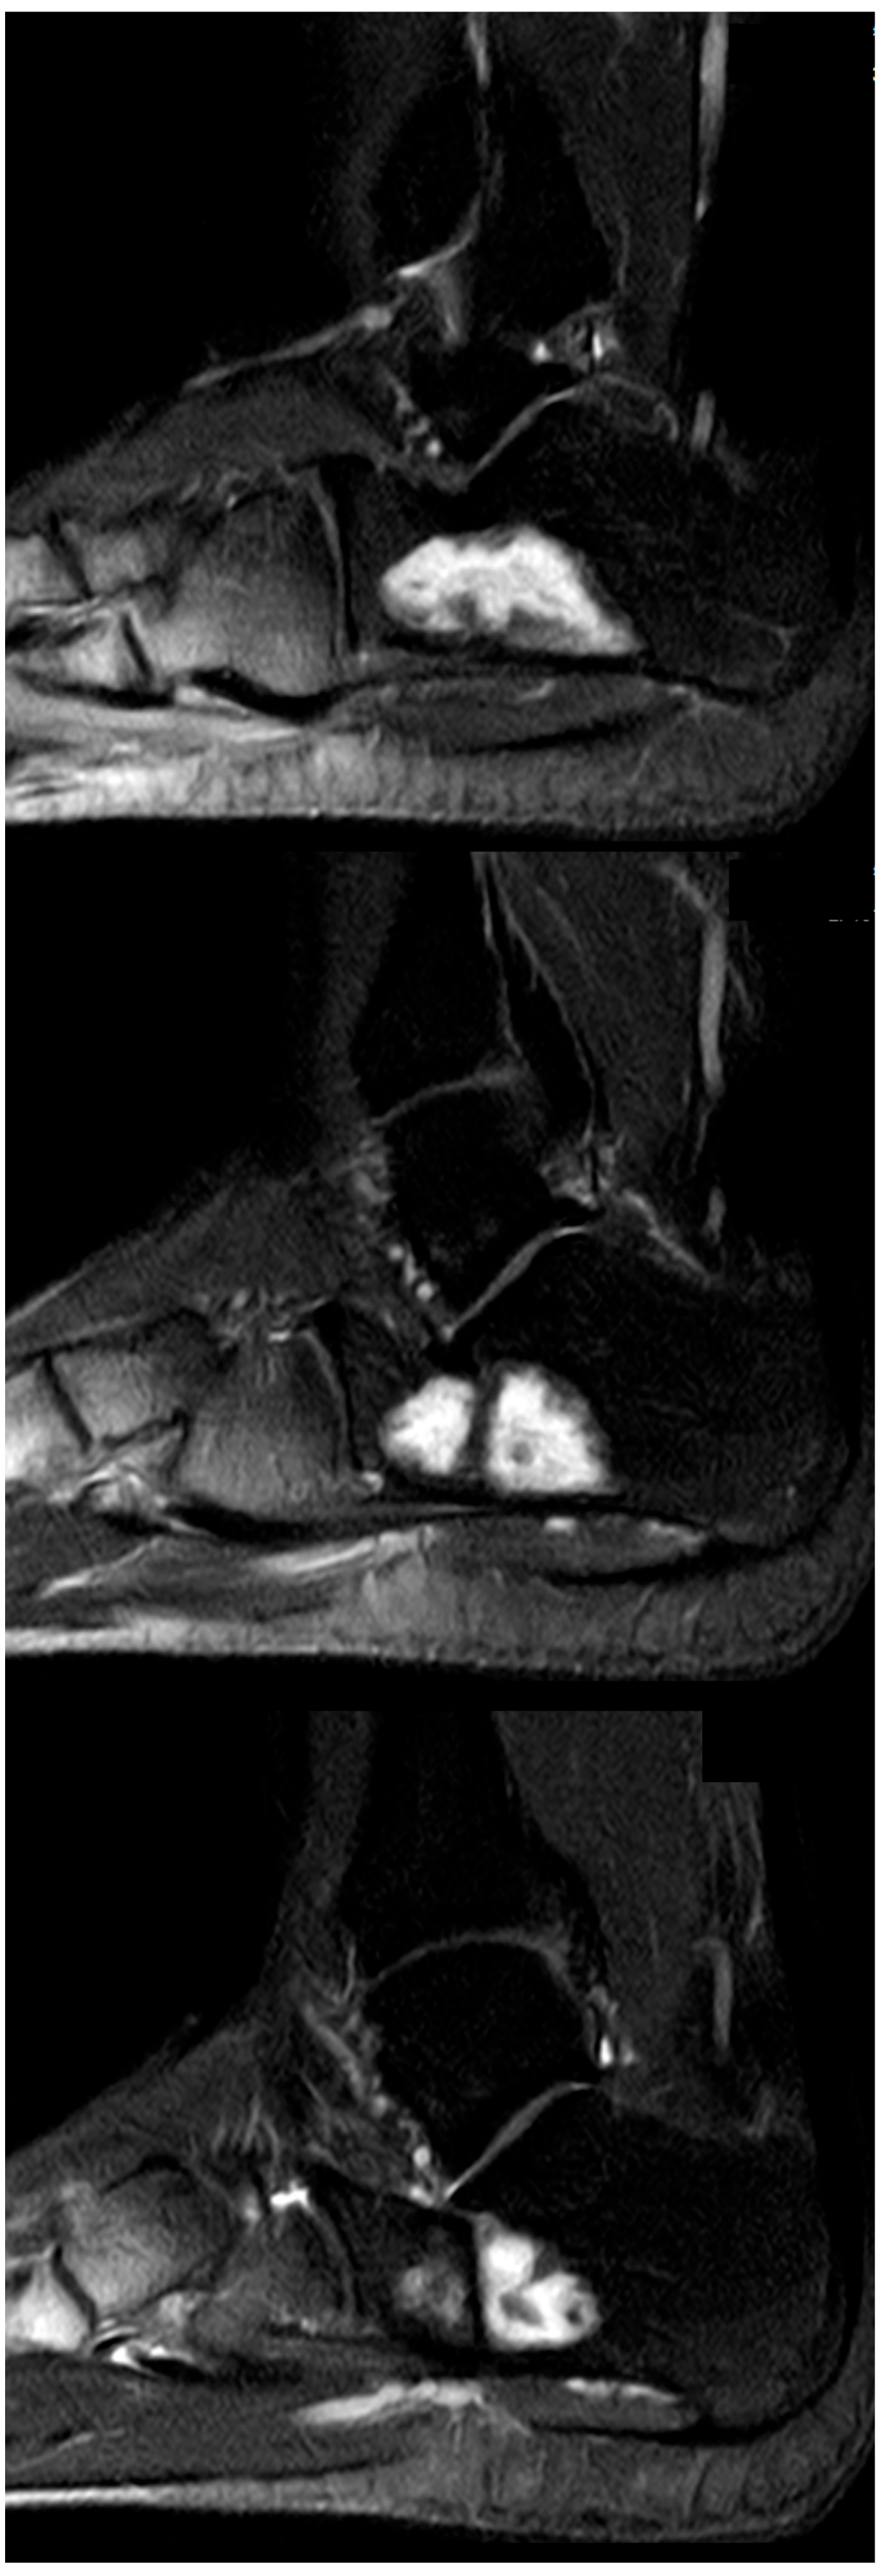

Figure 9.

Top, left to right: (a) preoperative X-ray of a large IOL, Milgram Stage 3 (case 22); (b) intraoperative fluoroscopy, postoperative radiographs at 6 (c) and 12 (d) weeks postoperatively showing continued loss of the filling material, consistent with persistent wound drainage. Bottom, left to right: (e) preoperative MRI, (f) sagittal MRI 12 months postop, (g) 20 months postop, and (h) 32 months postop. All MRI are sagittal T1 TIRM weighted.